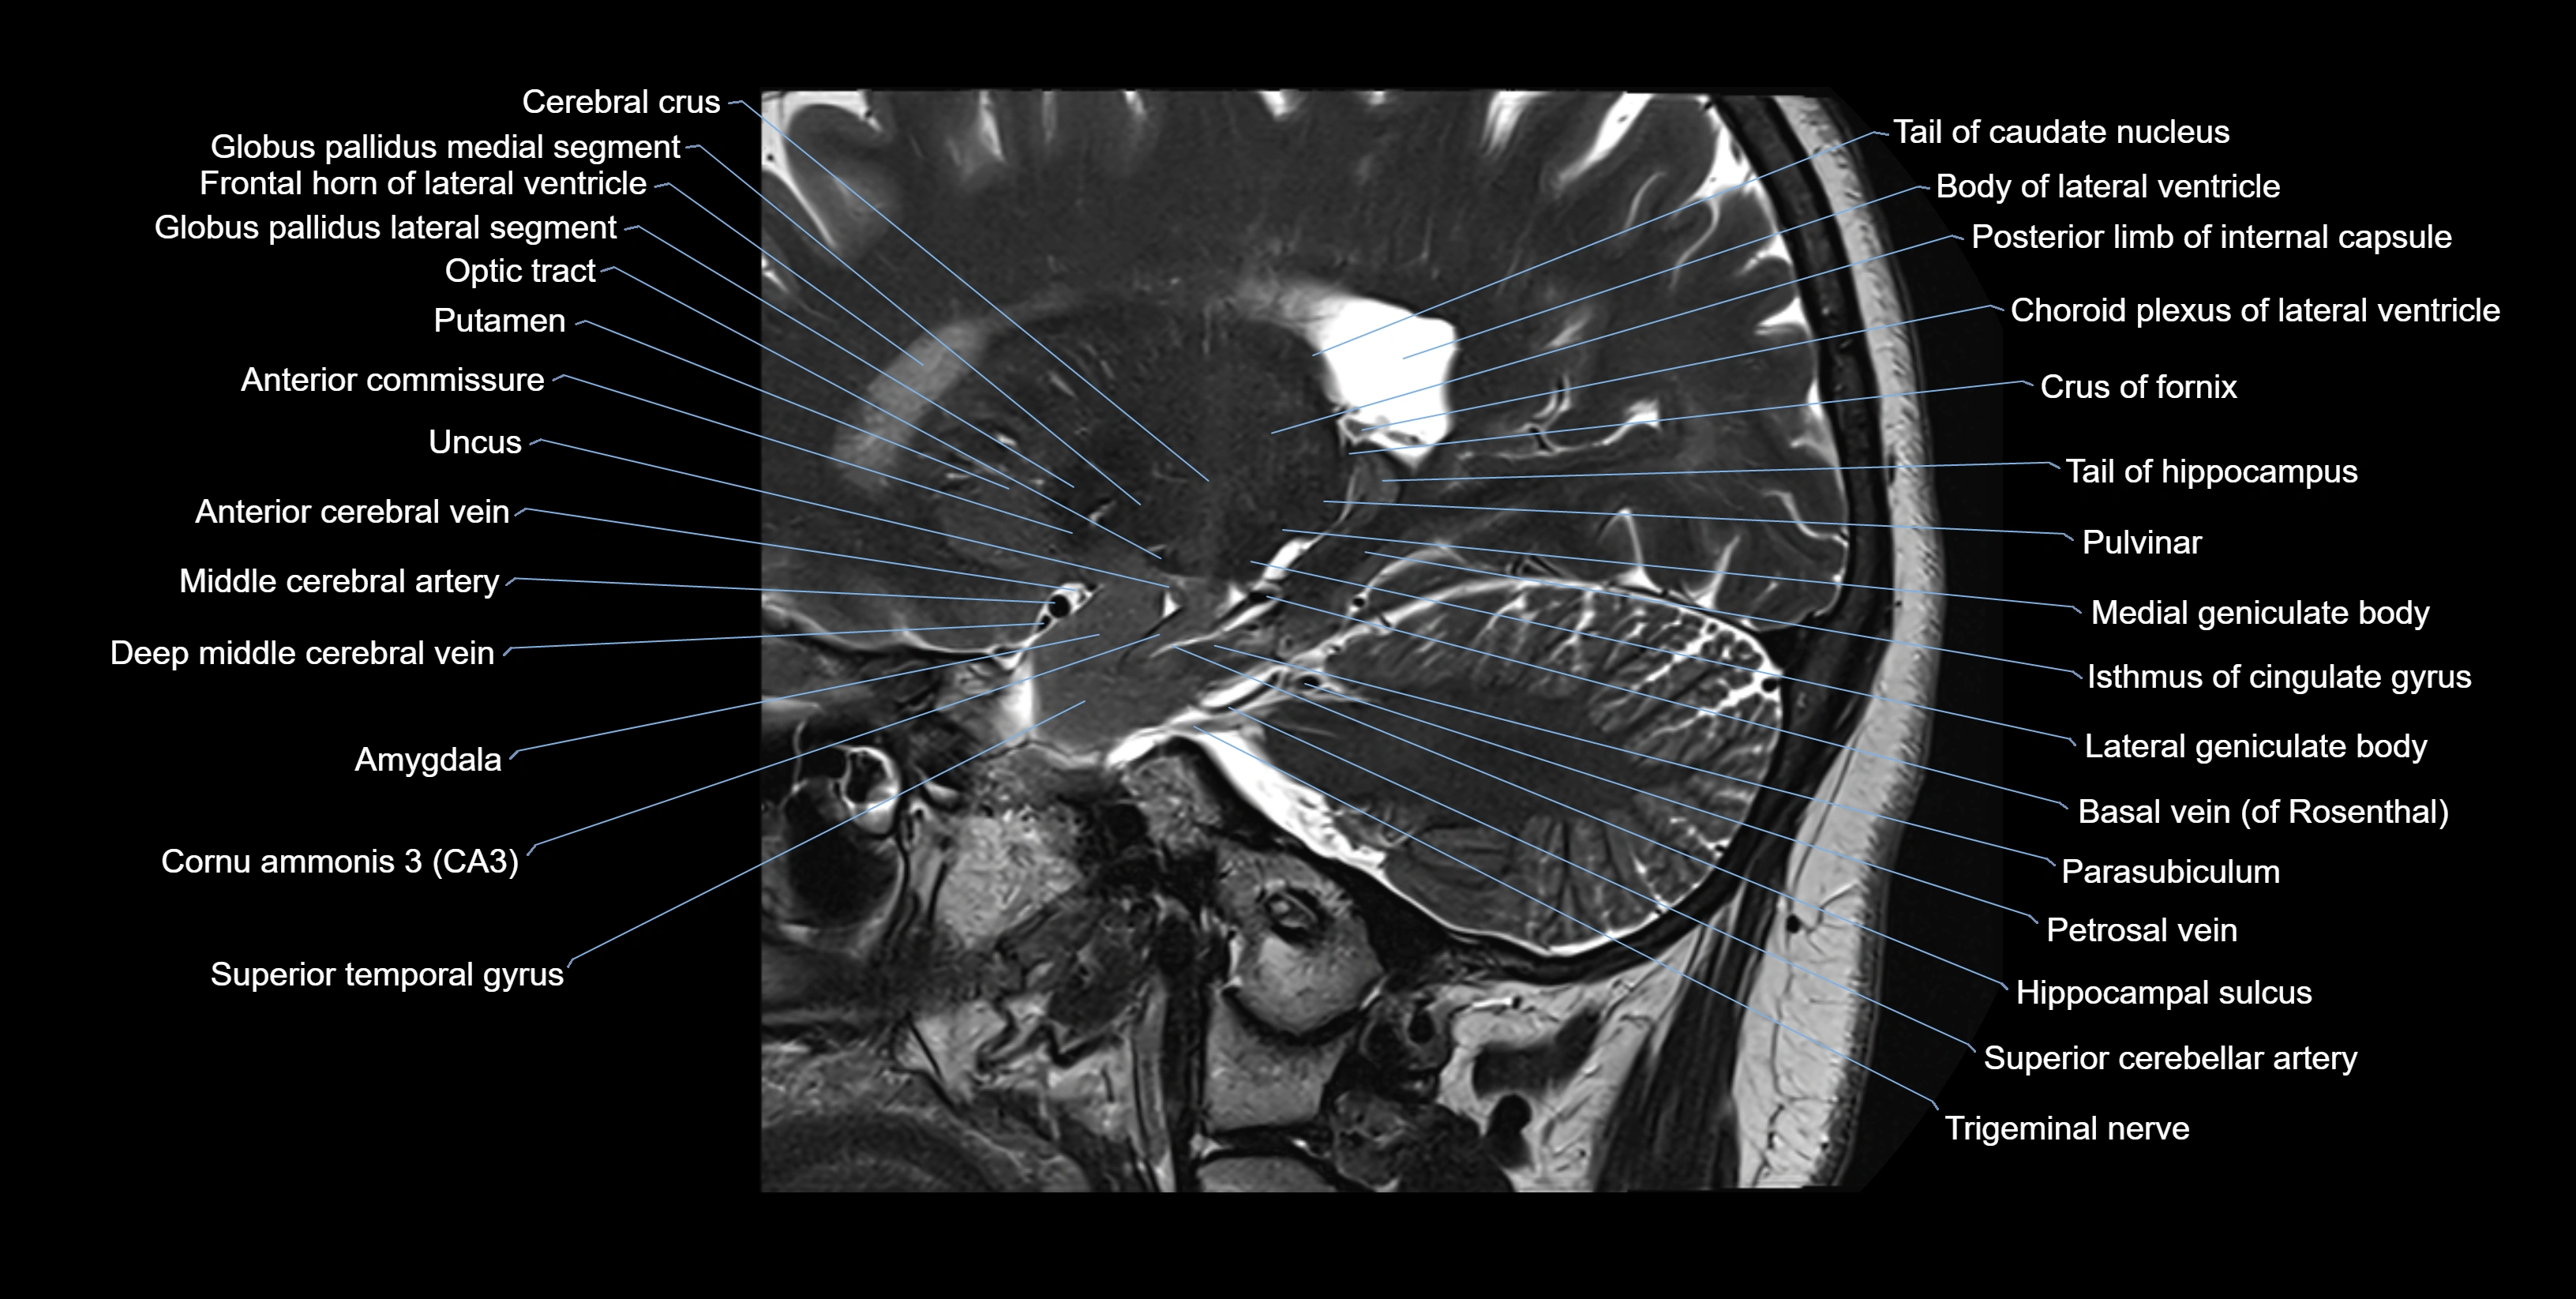

MRI images

image